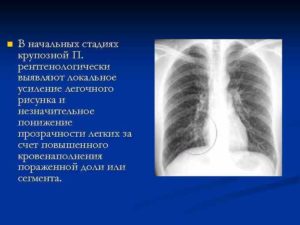

- пневмония – в начальной стадии и первое время после выздоровления легочное изображение локально усилено;